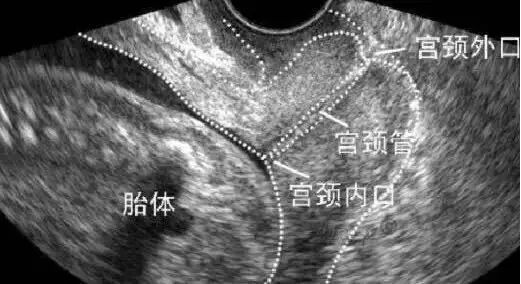

宫颈是子宫的大门,它分为内门、外门和中间的一个通道,承托着子宫。怀孕中期,胎儿逐渐长大、羊水量增多、子宫增大,宫颈负担加重。宫颈机能不全的孕妇,内门相对比较松弛,还没到足月分娩就提前打开了。内门越开越大,最后外门也会打开,宫颈全程开放。有些孕妇虽然宫颈内口(内门)还没开,但宫颈的长度(内外门中间的通道)明显缩短,预示着继续怀孕下去可能发生晚期流产或者早产。

另一个主要的诊断方法是孕期经阴道超声监测宫颈。如果发现宫颈长度小于25mm,宫颈内口呈现”Y”字型、“V”字型、“U”字型漏斗,就要小心了!